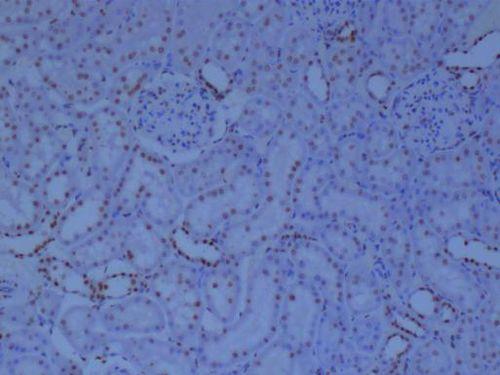

免疫组化,顾名思义,就是利用免疫学原理和分子生物学技术,对组织切片进行染色,以检测和定位组织中的特定抗原。简单来说,它就像是一把钥匙,能帮助我们找到隐藏在细胞深处的“宝藏”。

在这个视频中,我们可以看到,实验者首先将组织切片固定在载玻片上,然后进行抗原修复。这一步骤非常重要,因为只有将组织中的抗原暴露出来,才能让抗体与之结合。接下来,实验者使用特定的抗体和二抗进行染色,最后用显微镜观察结果。

第三个视频则展示了免疫组化在疾病研究中的应用。实验者通过一系列的实验,揭示了肿瘤细胞中特定抗原的表达情况,为疾病的诊断和治疗提供了重要依据。